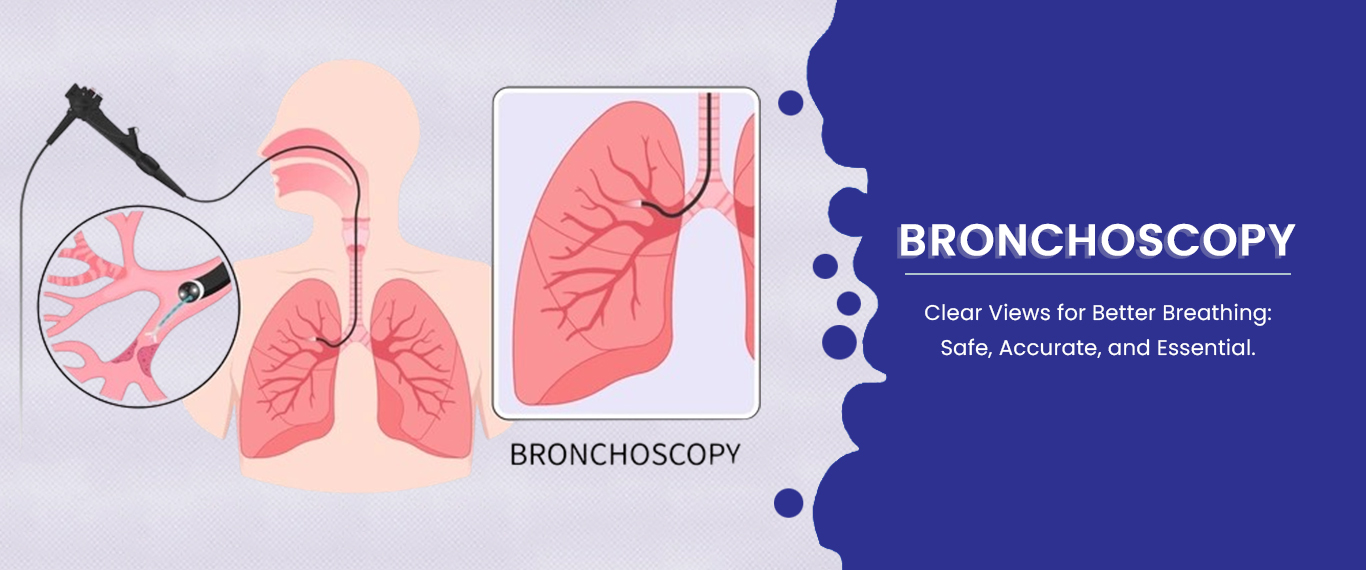

With advanced training and extensive experience, Dr. Priya is not only highly skilled in diagnosing and treating a wide range of lung conditions but is also proficient in cutting-edge bronchoscopic procedures. This means you can have confidence in receiving accurate diagnoses and effective, minimally invasive treatments when needed.